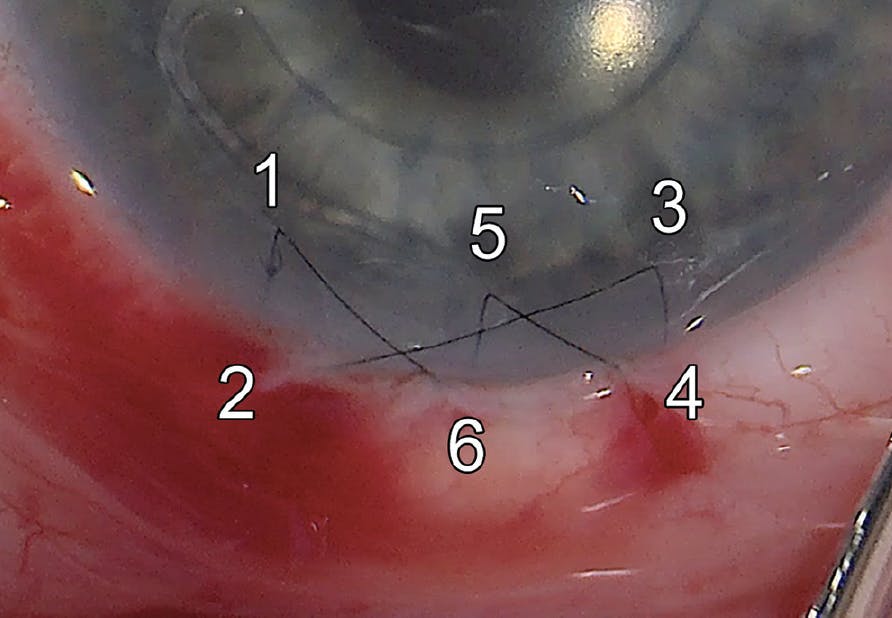

Current PMMA ACIOL models must be implanted through a large (approximately 6 mm) scleral tunnel or clear corneal wound. We perform clear corneal incisions and operate on the steep axis of the cornea to reduce astigmatism. We close the wound with a single 10-0 nylon suture in a cross-stitch pattern to spread out the radial forces and reduce surgically induced astigmatism (Figure 2). We recommend waiting at least 6 to 8 weeks before removing a suture for this size incision.

<p>Figure 2. To create a cross-stitch pattern for large corneal wound closure, we pass a single 10-0 nylon suture from point 1 to 2, 3 to 4, and 5 to 6. We tie the loose ends (points 1 and 6) together and rotate the suture to bury the knot.</p>

Figure 2. To create a cross-stitch pattern for large corneal wound closure, we pass a single 10-0 nylon suture from point 1 to 2, 3 to 4, and 5 to 6. We tie the loose ends (points 1 and 6) together and rotate the suture to bury the knot.